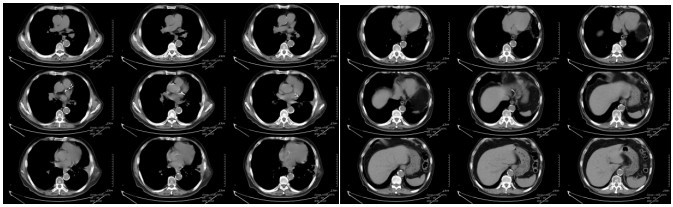

Chest CT on March 4, 2024 (1 month after carbon ion therapy): Left lung tumor 7.5 × 3.5 × 4.0 cm